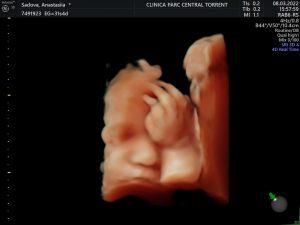

Imágenes asombrosas de tu bebé, captura cada detalle desde antes del nacimiento.

Nuestras ecografías permiten ver las emociones de tu bebé en la mejor calidad.

Somos un equipo especializado en imagen prenatal, ponemos a tu disposición espacios adaptados con la más alta tecnología en ecografías 5D y 4D en 8K, ahora tus ecografías con Hiperrealismo, al instante sin esperas.